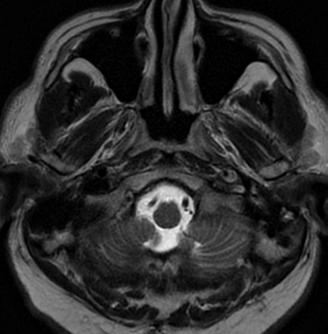

• Studiul opacifierii ramurilor corticale ale arterelor cerebrale medii (M4) drepte și stângi și a venelor cerebrale interne drepte și stângi (Fig.1).

Fig.1 ACTMS cranio-cerebrală, recon MIP în plan axial (a,b) și sagital (c): aspect normal; (a) opacifierea arterelor temporale dreaptă și stângă (săgeţi); (b) opaciferea ramurilor corticale ale arterelor cerebrale medii (M4)-săgeţi albe; opaciferea venelor cerebrale interne dreaptă și stângă (săgeţi negre-b și c).

Semiologie:

▶ Absența opacifierii M4 = 1 punct

▶ Opacifierea M4 = 0 punct

▶ Absența opacifierii venei cerebrale interne = 1 punct

▶ Opacifierea venei cerebrale interne = 0 puncte

• Un scor egal sau mai mare de 3 confirmă stopul circulator intracerebral. In acest caz, concluzia examinării este: „stop circulator intracerebral” care vine în sprijinul diagnosticului clinic de moarte cerebrală sau aspect ACT compatibil cu moartea cerebrală

• În caz contrar, concluzia examinării este „absența opririi circulatiei intracerebrale”, situaţie în care diagnosticul clinic de MC nu este confirmat.